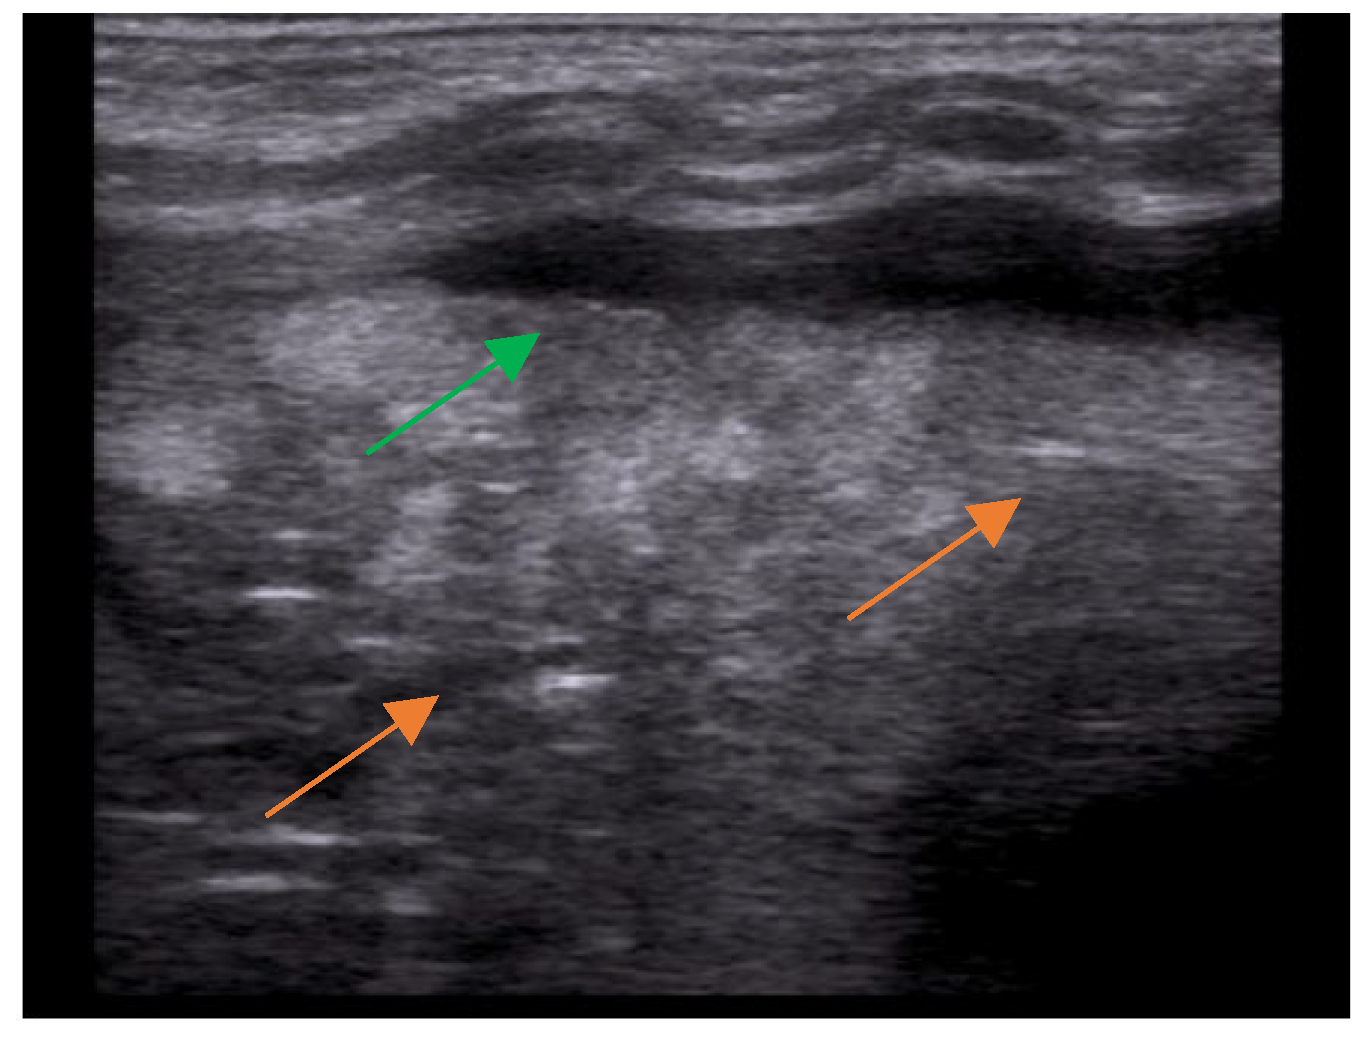

3. Lung Ultrasound: Where Do We Start

- The presence of A-lines.

- The presence of B-lines, their characteristics (short or long, spared or confluent) and their location (peri-lesional, monolateral/bilateral).

- The main lesion (consolidation): size, whether it is single or multiple, location (monolateral or bilateral). The presence of small subpleural consolidations (<1 cm).

- The presence of a bronchogram and its characteristics (air or fluid), morphology (branched or dot-like), dynamics during breathing (poorly or clearly dynamic); vascular pattern, presence of lung point and pulmonary pulse.

- The presence of lung sliding (M-mode).

- The presence and type of pleural effusion.